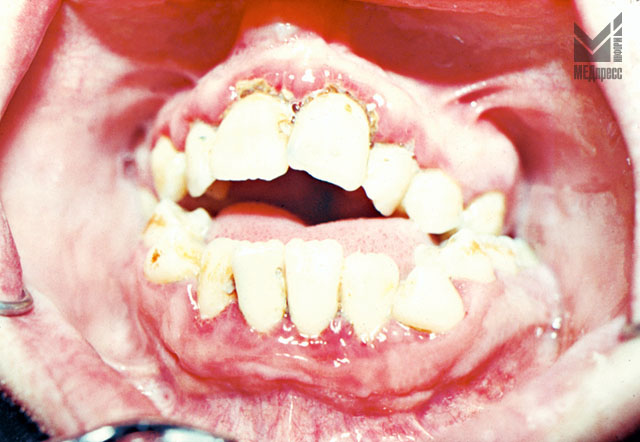

Рис. 8. При аномалийном расположении зубов. Тесное положение зубов. Гипертрофия межзубных сосочков у 31, 41, 42 зубов. Гиперемия, отек десневого края. Оголение шеек 32, 42 зубов.

Рис. 9. Тесное положение зубов. Отек и гиперемия десневого края у нижних резцов. Валикообразный десневой край у 31.